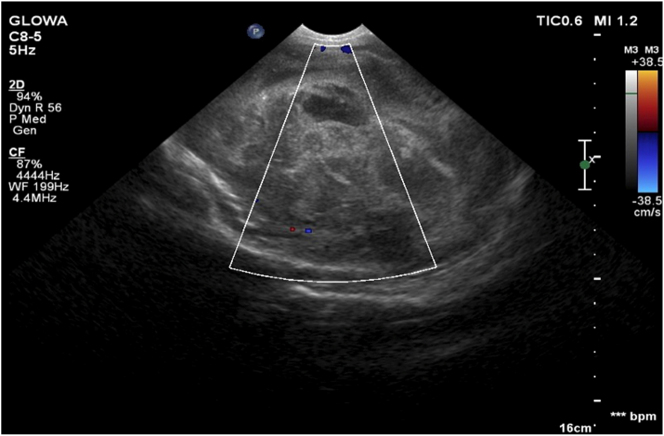

Case presentation: In the 29th week of pregnancy, a female fetus was diagnosed with intracranial hemorrhage complicated by hydrocephalus. Postnatal brain MRI imaging showed a solid proliferative lesion of the left hemisphere with dilatation of the ventricular system. Brown cerebrospinal fluid was collected during the puncture of the left lateral ventricle to reduce hydrocephalus. No tumor cells were detected by cytology. Due to increasing hydrocephalus, the patient was qualified for Rickham reservoir implantation. On day 27th, a craniotomy was performed to determine the etiology of recurrent prenatal intraventricular bleeding. During surgery, the bleeding mass raised the suspicion of neoplasm-histopathological examination of the retrieved tissue diagnosed WHO stage IV malignant glioma. The patient died at 8 months of age.

Abstract Image